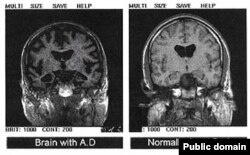

بيماری جنون و حواس پرتی اغلب اوقات، با از دست دادن حافظه، قدرت کلام و بيان و منطق و استدلال همراه است.

محققين گمان می کنند که در حالی که جنون و حواس پرتی بخش های ديگر مغز را مورد آسيب قرار می دهد، بخش های پيشانی و شقيقه ای عضله مغز، که عناصری از موسيقی نظير ريتم از طريق آنها دريافت می شوند، به گونه ای از آسيب ديدن درامان می ماند.